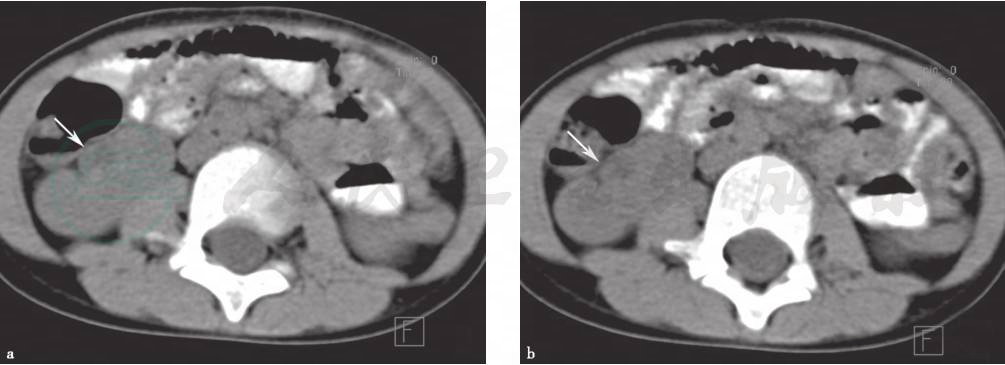

图1 肾旋转异常

a、b.CT平扫示右肾门指向前外侧(白箭),肾门增宽,肾实质密度、厚度未见异常